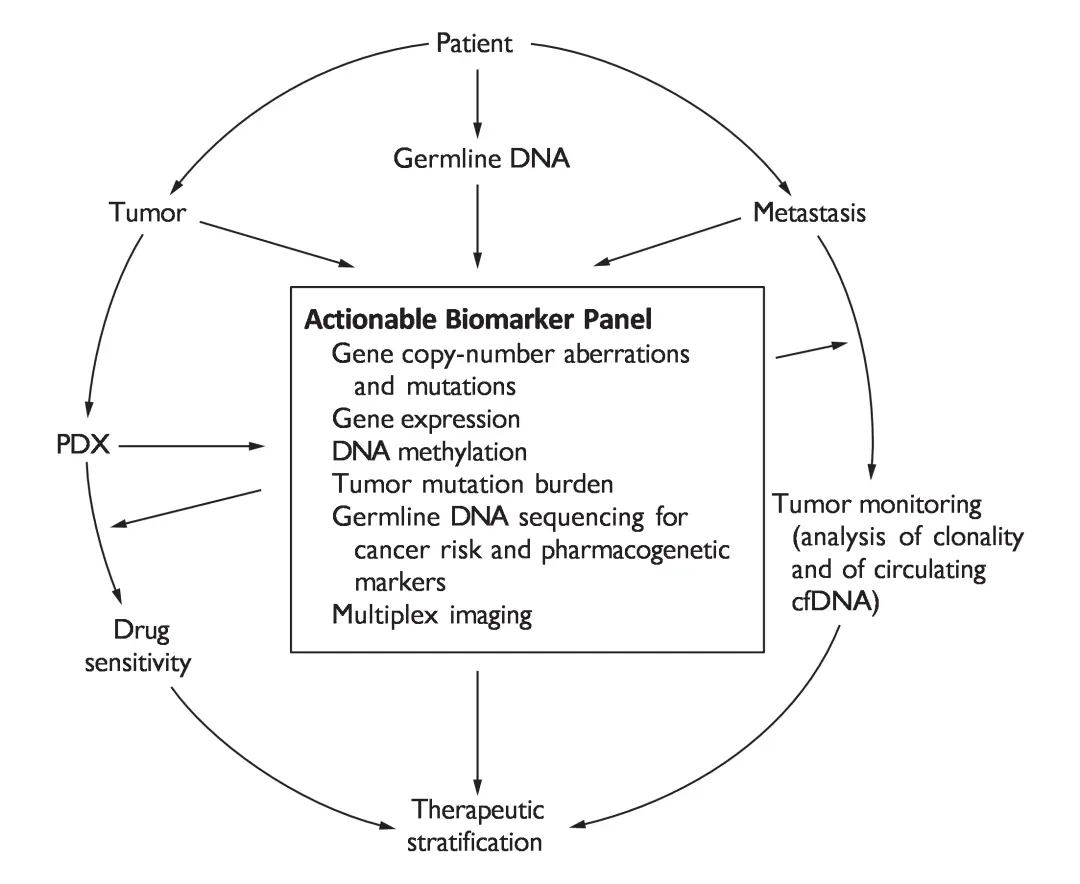

一旦确定了有效的药物,就要在所有新诊断的骨肉瘤患者中进行评估,这需要非常大的患者群体,来证明其明显超过60%的总生存率。针对这种罕见癌症的分子定义亚组患者,我们需要更精细的临床前肿瘤分类方法和更新的试验设计,以在有限的随访时间内在小亚群中寻求大的效果(图3)。

图3 骨肉瘤的分子信息精准医学之路。

【对生物样本进行分析,寻找新出现的、经过验证的、临床上可操控的生物标志物。通过使用大规模靶向测序技术,可以对肿瘤 DNA 和 RNA、正常种系 DNA 和转移性肿瘤(如果存在)进行表征。DNA 测序可识别基因拷贝数畸变和突变,RNA 测序可确定基因表达。DNA 甲基化分析可定量表观遗传标记。通过 DNA 测序计算出的肿瘤突变负荷可用于识别具有超突变的异常肿瘤,这些肿瘤可能对免疫检查点抑制剂产生异常反应。种系 DNA 测序可识别癌症风险变异,及其对患者和家庭的影响,并可预测异常反应或毒性作用的药物遗传学标记。该信息将用于临床试验中的治疗分层。如果有合适的样本,可以开发患者来源的异种移植物(PDX)用于药物敏感性测试,其结果将进一步为患者分层提供依据。多重组织成像研究提供了对浸润炎症细胞的类型和数量的测量方法,这为基因表达数据的分析提供了有力补充。最后,在治疗过程中,将转移性和复发性疾病的样本与原发性肿瘤进行比较,有可能识别出临床相关的差异。这些样本的克隆性分析将为肿瘤进化提供广阔的视野。循环游离 DNA (cfDNA) 的微创分析将为了解肿瘤缓解提供一个渠道。】